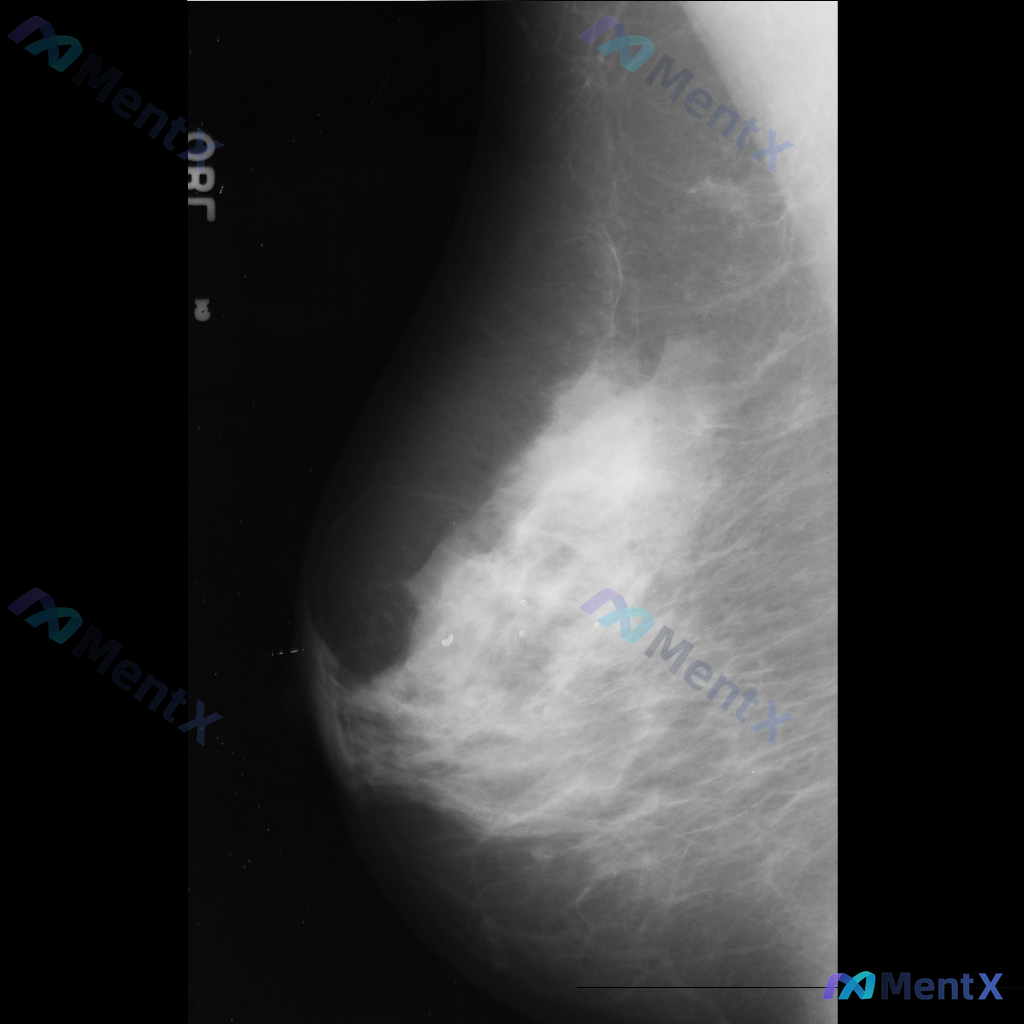

这张乳腺钼靶影像的异常,用什么术语描述最准确?

整理到一张乳腺钼靶影像的讨论资料,右乳可见一处病灶。

想先请大家看看:针对这张影像的异常表现,用什么术语描述最准确全面?另外结合征象,第一反应会往哪个方向考虑?